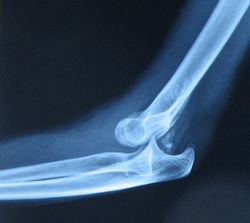

Contributor: Aaron Lessen, MD Educational Pearls: What is a Nursemaid's Elbow? A condition in which an elbow gets partially pulled out of place (a radial head subluxation) Usually happens in kids under 5 because the ligaments around their elbow are still loose. A common situation is when an adult pulls a child up by the hand or swings them by the arms. The sudden tug causes the radius to slip out of its normal spot at the elbow joint. How are they identified? These don't normally need an xray The child will often hold their arm close to their side and refuse to use it There's usually no swelling or obvious deformity. Treatment? Reduce the radial head subluxation. There are two possible techniques: Flexion and supination. Start with the arm extended and pronated. Then supinate the forearm. Then bend the elbow up all the way. Hyper-pronation. One hand stabilizes just above the child's elbow, the other holds the wrist. Start with the arm extended. Hyperpronate the forearm. Listen/feel for a click The child is normally back to normal quickly, if not get the xray Which is better? Hyperpronation (Aksel, 2025) 10% first attempt failure rate Flexion-pronation has a 25% first attempt failure rate References Aksel G, Küka B, İslam MM, Demirkapı F, Öztürk İ, İşlek OM, Ademoğlu E, Eroğlu SE, Satıcı MO, Özdemir S. Comparison of supination/flexion maneuver to hyperpronation maneuver in the reduction of radial head subluxations: A randomized clinical trial. Am J Emerg Med. 2025 Feb;88:29-33. doi: 10.1016/j.ajem.2024.11.026. Epub 2024 Nov 18. PMID: 39579408. Ulici A, Herdea A, Carp M, Nahoi CA, Tevanov I. Nursemaid's Elbow - Supination-flexion Technique Versus Hyperpronation/forced Pronation: Randomized Clinical Study. Indian J Orthop. 2019 Jan-Feb;53(1):117-121. doi: 10.4103/ortho.IJOrtho_442_17. PMID: 30905991; PMCID: PMC6394198. Summarized by Jeffrey Olson, MS4 | Edited by Jeffrey Olson and Jorge Chalit, OMS4 Donate: https://emergencymedicalminute.org/donate/